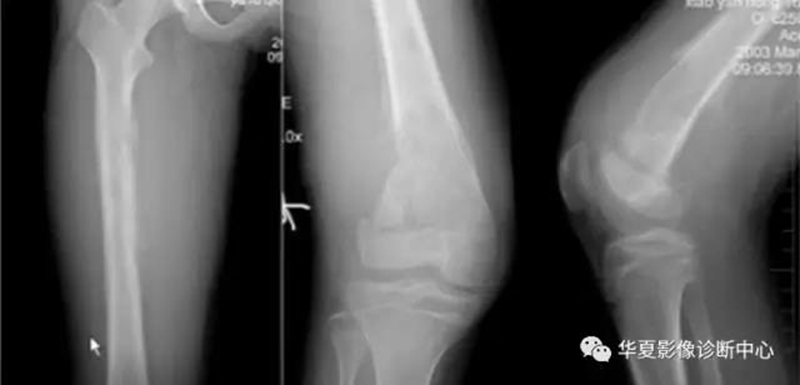

左为亚急性化脓性骨髓炎,右为骨肉瘤

左股骨上段囊状骨破坏区,边缘光滑,无硬化边

股骨远端正常骨骺,侵犯骺板软骨:出现软组织且宽窄不一